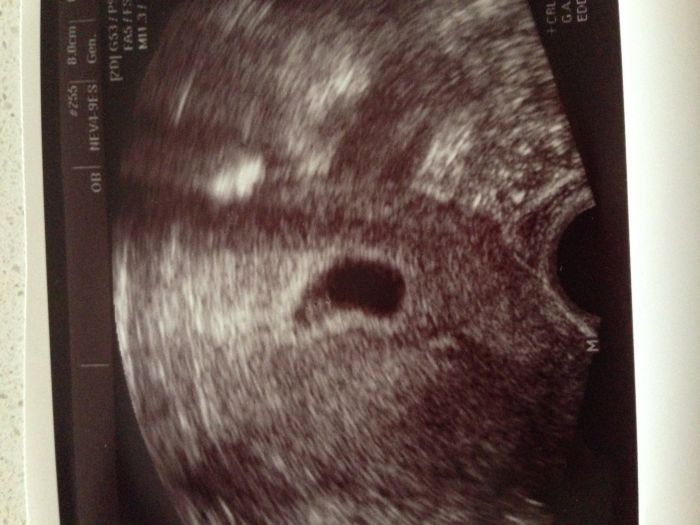

Ještě přidávám první foto

Ahojky, vítám nové tehulky :) Alishe , je to pěkně vidět, ja už se nemůžu dočkat na kontrolu, i když mi nervy stále pracují... Já brala od února kyselinu listovou a dr mi doporučil po potratu vitamíny Chytré miminko , je to zelena krabička, bere se to na začátku těhotenství, ja tedy na doporučení začala dříve a v polovině se přechází na krabičku fialovou, obsahuje to kyselinu listovou a další vitamíny, co jsou potřeba :) jinak holky, máte nějakou zkušenost s čaji pro těhotné? Jeden jsem dostala, ale nedočetla jsem se k čemu je to dobre

teda, uz to jde pekne videt. ja se taky tak tesim jsem zvedava jak to tam bude vsechno za tech 14 dni videt.

[587015] my máme s manželem v rodině oba dvojčata, ale naši kluci jsou jednovaječní a jednovaječné dvojčata prý dědičné nejsou. Hned jsem se ptala, kolik jich tam je Smile teď viděl jedno, ale prý to ještě není 100%, u kluků to poznali až 9tt, měli společný obal i placentu. Doufám, že to u jednoho zůstane.

Podle doktora bych měla být 6tt.

Ahoj holky, všem Vam gratuluji k těhotenství, moc rada bych se k Vam připojila, TP bych mela mit asi 9.3.2015, na 1. kontrolu jsem objednána az za 14 dni, ale uz ted se nemůžu dočkat. Koukám, ze některé z vas uz byly u dr. a Alishe ma i krásný foto z uzv, wau, vy se mate;-)